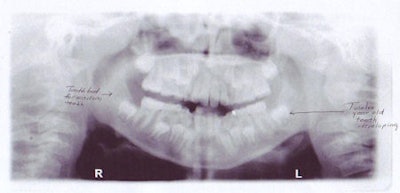

| Above, panoramic x-ray of a 9-year-old shows the mixed dentition typical of someone that age. Below, panoramic x-ray of a 16-year-old shows the formation of third molars. All images courtesy of Sandra Swing, D.D.S. |